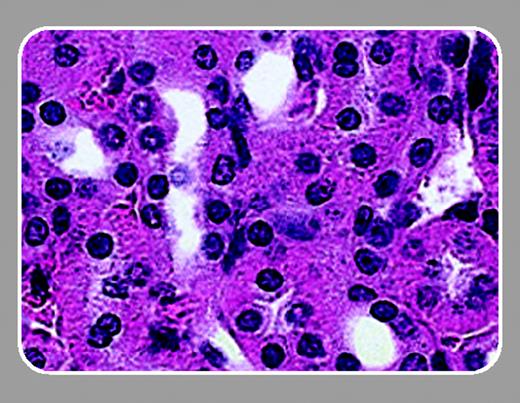

In this issue of Blood, Lavasseur and colleagues (page 4312) have followed up on the original description of successful correction of SCD in the mouse model. Similar to Pawliuk et al,5 Lavasseur et al demonstrate that lentivirus-mediated gene transfer of a modified human β-globin gene could inhibit the sickling of mouse SCD erythrocytes. In addition, they describe significant improvements in all clinical parameters measured, including liver and spleen necrosis and kidney function.

Lavasseur et al make 3 important points that should interest the readers of Blood. First, they have refined both the mouse model and the lentivirus vector. This group has developed an inbred SCD mouse model that allows transplantations to be done without the complications of graft-versus-host disease. In addition, Lavasseur et al used inbred SCD mice as both donors and recipients, ensuring that there were no normal mouse erythrocytes in the circulation. Thus, the improvements seen in the animals were the direct result of the globin transgene. Lavasseur et al also engineered the human β-globin gene to produce more potent antisickling activity and a greater affinity for α-globin.